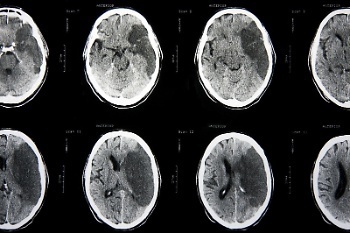

Traumatic Brain Injury May Raise Stroke Risk

New studies show that in the future, traumatic brain injuries may add an extra risk of stroke. After undergoing a traumatic brain injury, compared to those who just go through a trauma, people gain an extra 30% chance of experiencing a stroke.

Experiencing a traumatic brain injury could raise your risk of having a stroke in the future, a new study suggests. Researchers from the University of…